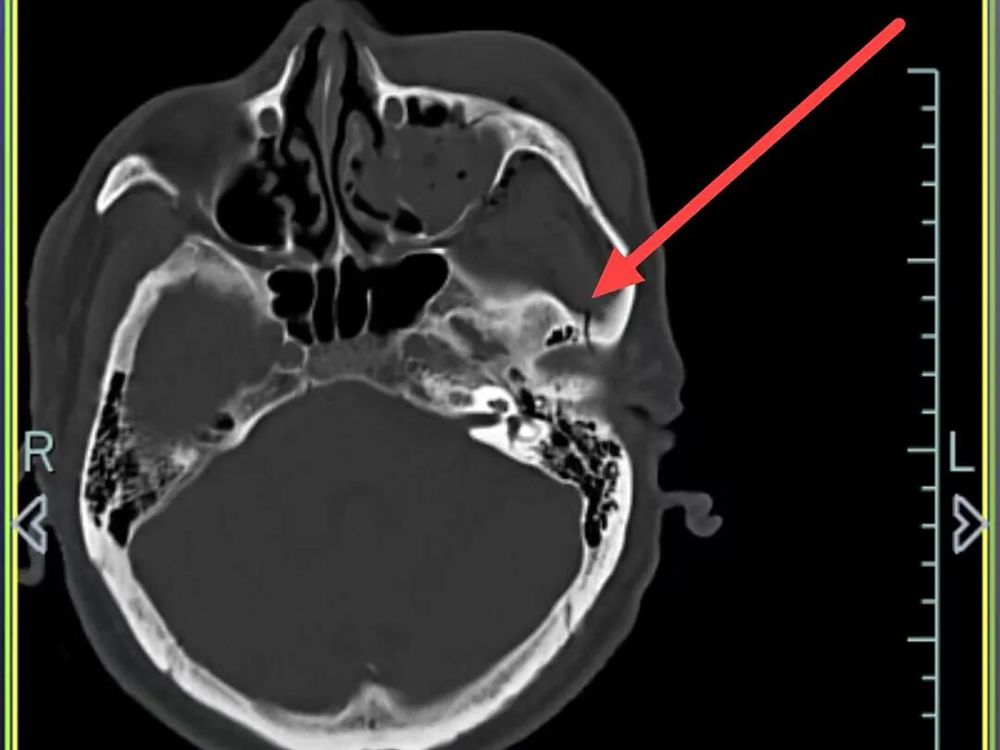

医院快速开通绿色通道并完善一系列检查后,诊断结果令人揪心:孙先生患有重型闭合性颅脑损伤,包括多发性创伤性脑出血、右侧颞部创伤性硬膜下出血、创伤性蛛网膜下腔出血以及脑震荡,同时合并多处骨折及软组织挫裂伤。

外侧壁、左眼眶外侧壁骨折、左侧颌面部软组织肿胀,软组织内积气

左侧颞骨、左侧颧弓、左侧上颌窦前壁骨折